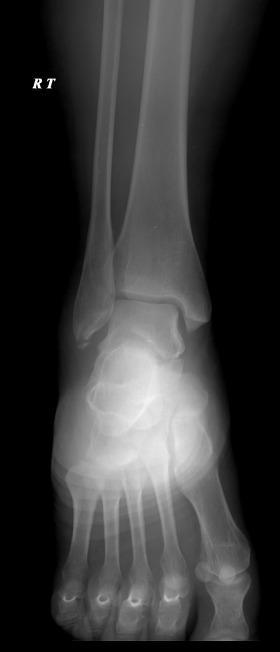

Radiopaedia.org. From the case rID: 209862

Entorse grave LCL = avec arrachement osseux

- Rechercher un diastasis tibio-talien sur la radio (entre malléole interne et talus).

- Rechercher une fracture de Maisonneuve (association entorse LCM et fracture col fibulaire) : demander radio de jambe.